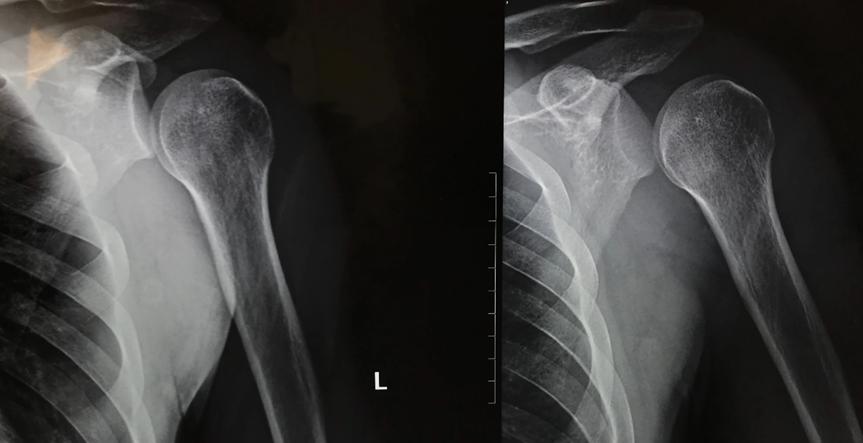

肩关节主要由肱骨(肱骨头)与肩胛骨(肩胛盂)连接构成,周围分布有韧带、肌肉固定。肩关节脱位习惯上常指肱盂关节脱位,当肩部受到外力打击(多为间接*力暴**),肩部关节骨骼与骨骼相连的关节结构发生了错位,骨骼被迫离开了正常的位置,肱骨头突破关节囊而发生脱位,临床上常表现为肩部疼痛、肿胀以及肩关节活动障碍等症状。

肩关节脱位不同类型,症状并不完全一致。患者主要表现为肩部疼痛、肿胀及肩关节活动障碍。当肩部受力时疼痛症状加重,为减轻疼痛患者常处于自然保护体位,检查时可发现患肩呈方肩畸形。可能会伴发肩部骨折及腋丛神经、臂丛神经损伤。

2、局部症状;受伤后患者临床表现为肩部疼痛、肿胀、畸形、肩关节活动障碍,当患者肩部受力时疼痛加重。检查时可发现患肩呈方肩畸形,患肩失去正常饱满圆钝的外形呈“方肩”样形态,肩峰到肱骨的距离多增加。

3、肩关节空虚;关节盂空虚,除方肩畸形外,触诊发现肩峰下空虚,可在腋窝、喙突或锁骨下触到脱位的肱骨头。